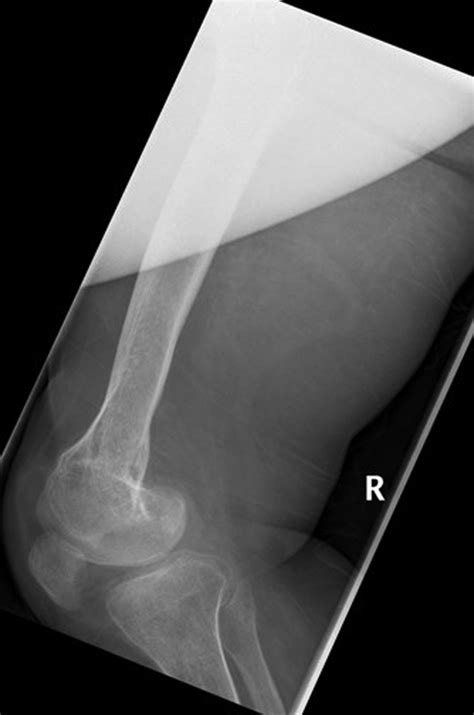

• Musculoskeletal Abnormalities: Limb hypoplasia (underdevelopment of limbs) and muscle weakness are common.